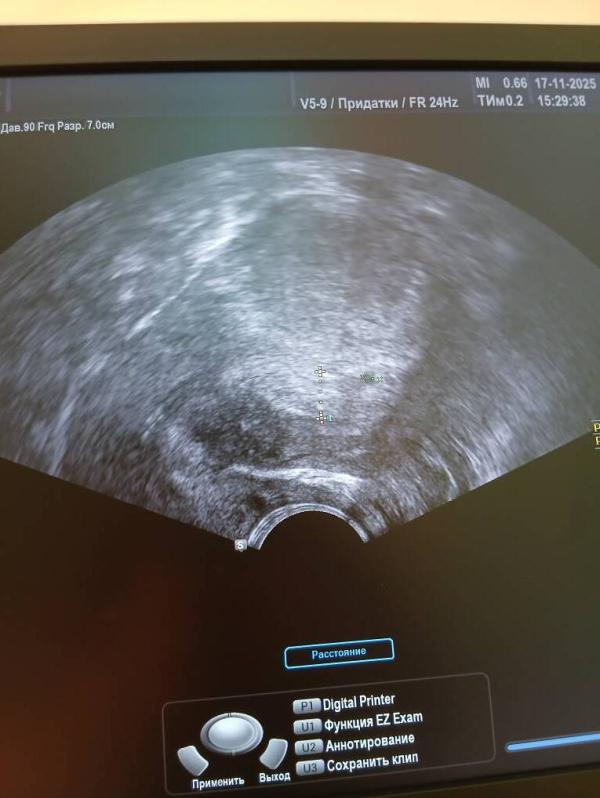

Да даже врачи в замешательстве провели консилиум. была на 3 узи сегодня опять отправили на узи